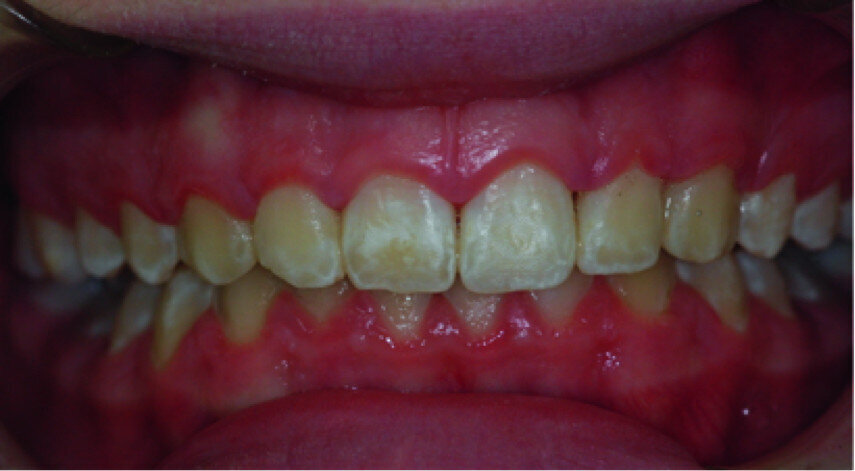

Clinical view just after surgery.

Healing five days after surgery.

A 14-year-old female patient was referred to our department by the orthodontics unit because, at the end of fixed orthodontic treatment, she had developed gingival enlargement in the upper arch (Fig. 1), probably related to the fast closure of the spaces associated with very poor oral hygiene due to bleeding during toothbrushing. Just after the removal of the appliance, a topical anaesthetic (EMLA, AstraZeneca) was applied to the gingivae (Fig. 2) and a gingivectomy was performed using a diode laser (XD-2, Fotona) according to the technique of removal of the inter dental papillae (Fig. 3). The parameters used were as follows: a wavelength of 808 nm, 3 W in continuous wave, a 320 μm fibre in contact mode. The intervention had a duration of 375 seconds, and the patient did not feel any pain (Fig. 4). After the intervention, the patient did not take any kind of pain medication, and the healing process was completed in five days (Fig. 5).